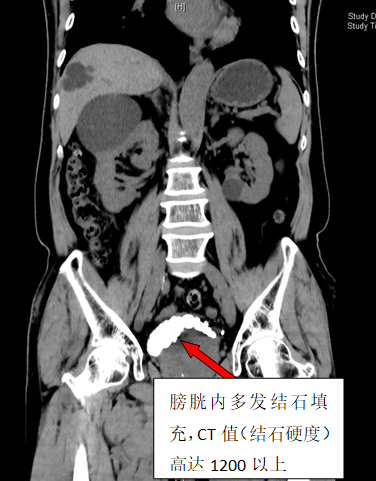

79岁李雄(化名)四年来一直被反复的尿频、血尿、下腹胀痛不适所困扰。在家人多次劝说下,他来到维多利亚老品牌76696vic泌尿外科二区就诊。CT检查结果显示李大爷膀胱内布满了30余枚结石,犹如月球表面的环形山,其中最大的那颗直径达3厘米,几乎占据了膀胱1/3的空间。

手术当天,泌尿外科二区团队凭借精湛的技术和丰富的经验,为李大爷实施了经尿道钬激光碎石手术。整个碎石过程历时2小时,医护人员精准操作,共发出13800次激光脉冲,将30枚结石打碎取出。术后CT三维重建显示,李大爷的膀胱腔隙内结石已清除干净。